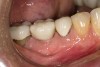

Case Presentation

A mandibular right first molar was extracted due to an advanced Class III furcation and an irreversible pulpitis—a combination lesion. An immediate implant placement protocol was elected, and a PEEK abutment was placed on the implant (Figure 1). After 3 months of healing, a scan body was placed on the osseointegrated implant (Figure 2 and Figure 3), and an intraoral scan was taken (TRIOS Pod) (Figure 4) for the fabrication of a screw-retained crown.

Fig 1. Immediate implant placement with a PEEK healing abutment to contour soft tissue, mandibular right first molar.

Figure 1